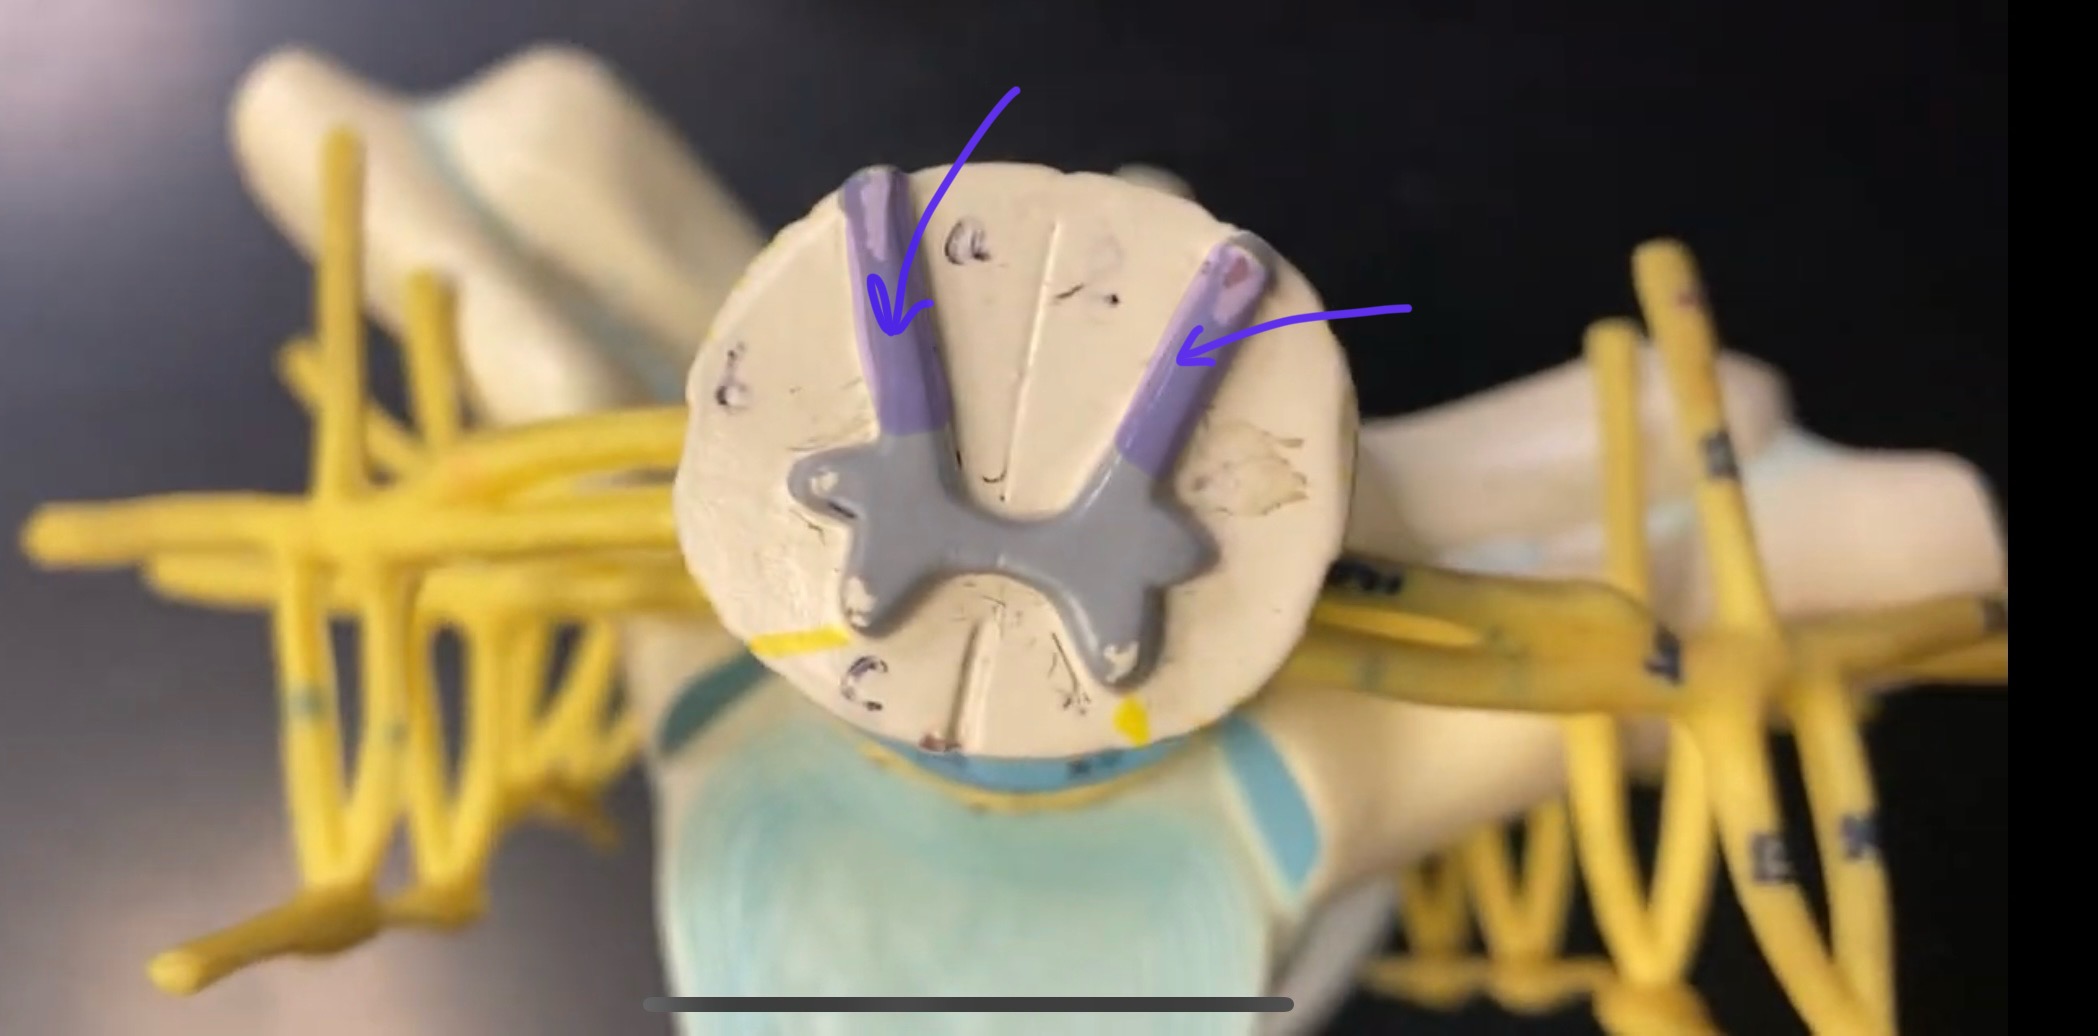

posterior (dorsal) horn

posterior (dorsal) horn; R—>L

anterior (ventral) horn

posterior (dorsal) root ganglion

What is the bulb here?

posterior (dorsal) root ganglion

posterior (dorsal) root

posterior (dorsal) root

anterior (ventral) root

anterior (ventral) root